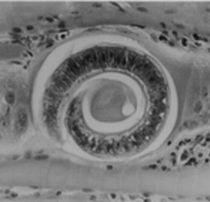

豚の胃にみられますが、雄は粘膜面に、雌は粘膜の腺窩に虫嚢を作って寄生します。

シモンド豚胃虫 ~ 豚の胃にみられますが、雄は粘膜面に、雌は粘膜の腺窩に虫嚢を作って寄生します